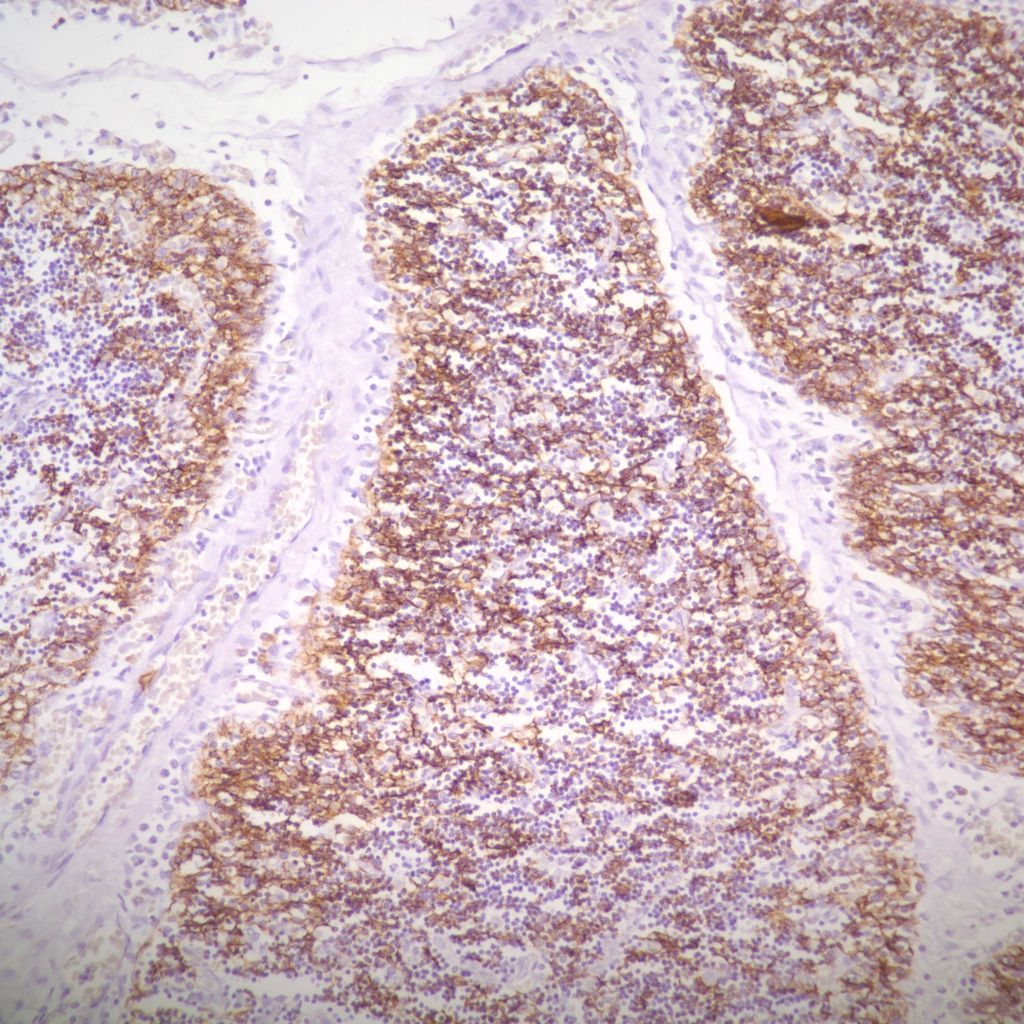

The complexity of thymic changes is demonstrated in a case of a 22 week gestation infant with a week of preterm premature rupture of membranes who was treated with betamethasone (a synthetic corticosteroid that can cross the placenta to the infant and used to promote lung maturation) and antibiotics. The infant survived for three quarters of an hour. The placenta demonstrated choroamnionitis with some fetal inflammation in the superficial chorionic vessels. The autopsy demonstrated complete involution of the thymus, follicular formation in the spleen, and extensive, intense acute pneumonitis with no growth of microorganisms on lung culture. The thymus demonstrated an inverted picture with no cortex and small lymphocytes in the medulla. The cortical rim demonstrated a compact epithelial layer. (Figs 16, 17) This infant had evidence of acute inflammation, and antibody stimulation, making it impossible to assess the changes due to the exogenous steroid.

The fetal thymus is the site in which immature thymic lymphocytes enter the outer cortex, mature into double positive CD4+ and 8+ cells, and then as single positive lymphocytes in the medulla are released into the blood as single effector or helper phenotypes. This process is guided by thymic epithelial cells and the chemokines. Immature lymphocytes can be negatively selected, for example, unable to bind to MHC antigens, and die. Presumably these cells are phagocytosed by macrophages and dendritic cells in the cortex and medulla. In the medulla, specialized cells present self-antigens. Cells that bind strongly to these antigens undergo apoptosis. There is normally a high proliferation and turnover of lymphocytes. The appearance of loss of cortical lymphocytes in accelerated involution could be some combination of decreased influx of immature cells, more rapid negative selection (as suggested by phagocytosis of lymphocytes in the cortex and medulla), or even more rapid processing and efflux of mature cells. The consequences of continuous stress over acute stress on the future T-lymphocyte population is also unclear. An analysis of thymuses removed at less than one month of age at cardiac surgery from infants without exogenous cortisol, found that by one day of age there was a marked reduction in the level of double positive T cells. This suggests that some of the changes accelerated by corticosteroids may be the same as normal changes following delivery [21]. Interestingly, the thymus is commonly removed at the time of cardiac surgery, without apparent ill consequences. Similarly, adults usually have complete involution of the thymus without consequence.